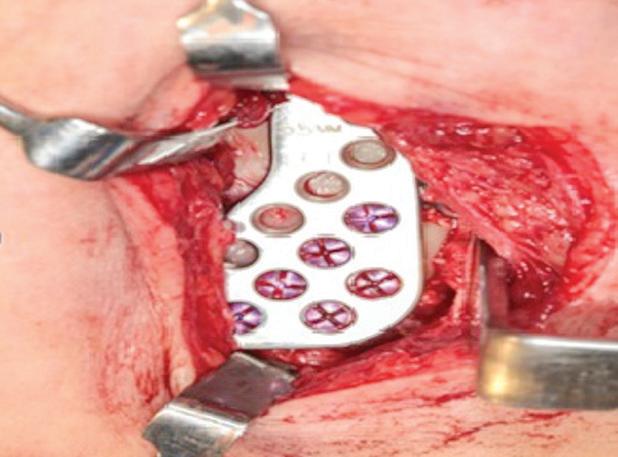

A paciente foi submetida à reconstrução total bilateral com próteses de estoque do sistema Biomet (Biomet 3i do Brasil Ltda., São Paulo/SP, Brasil). Foram realizados, bilateralmente, acessos pré-auricular e retromandibular, condilectomia e, por fim, instalação das próteses de estoque. A sequência da instalação das próteses consistiu em primeiro o componente fossa e, depois, o componente mandibular (Fig. 2). O paciente encontra-se aos cinco anos de pós-operatório, com uma boa abertura de boca e oclusão preservada e sem dor (Fig. 3).

Figura 2: A) Acesso pré-auricular direito. B) Acesso pré-auricular esquerdo. C) Componente mandibular direito instalado na face lateral do ramo da mandíbula através do acesso retromandibular. D) Componente fossa direito instalado na base do crânio através do acesso pré-auricular. E) Componente mandibular esquerdo instalado na face lateral do ramo da mandíbula através do acesso retromandibular. F) Componente fossa esquerdo instalado na base do crânio através do acesso pré-auricular.